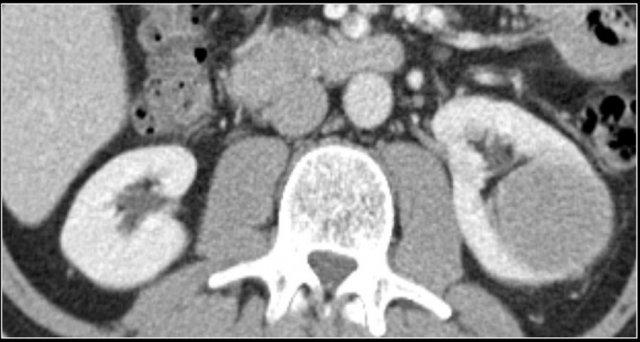

Ở thì vỏ-tủy (corticomedullary phase), cấu trúc vỏ-tủy bình thường trong các giả u này có thể được nhận diện rõ ràng, giúp phân biệt chúng với các tổn thương thực sự.

Giả u (Pseudotumor). Thì thận (Nephrogenic phase) ở bên trái và thì vỏ-tủy (Corticomedullary phase) ở bên phải.

Đây là một trường hợp khác.

Ở thì thận, có thể đặt ra nghi vấn về sự hiện diện của một tổn thương ở thận trái.

Tuy nhiên, ở thì vỏ-tủy, rõ ràng đây là một giả u (pseudotumor).